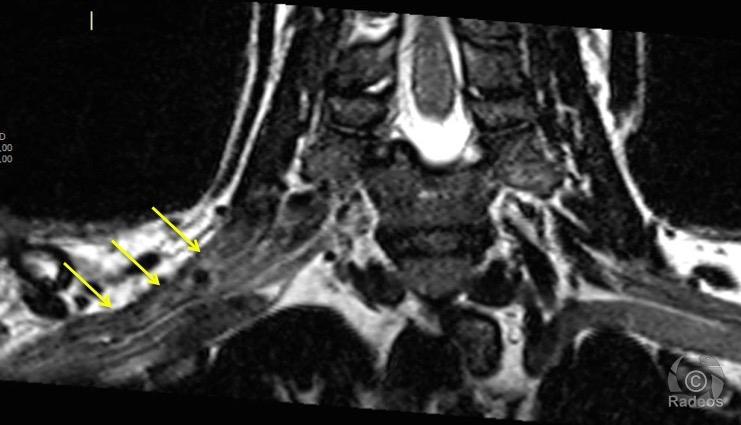

ETUDE CLINIQUE ( IMAGERIE )

L’étude de l’anatomie du plexus brachial est indispensable vue la diversité de la pathologie

- Traumatique dans les lésions nerveuses du plexus brachial et ces branches collatérales

- Infectieuse

- néoplasique dans le cas des tumeurs des parties molles

- Un intérêt sémiologique dans les explorations fonctionelle

INTERET SEMIOLOGIQUE

–paralysée du plexus brachial

- le plexus brachial peut subir des lésions entrainant des paralysies partielles ou totales

- Avulsion , arrachement des racines de plexus brachial

- ou une rupture de nerf

-C’est une paralysie traumatique du plexus brachial survenant au moment de la naissance, consécutive le plus souvent à un accouchement difficile. Il existe des paralysies obstétricales du plexus brachial consécutives à une césarienne s’expliquant par une malposition utérine chez le gros fœtus.

IMAGE CADAVERIQUE